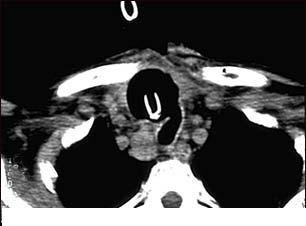

Cancerul tiroidian